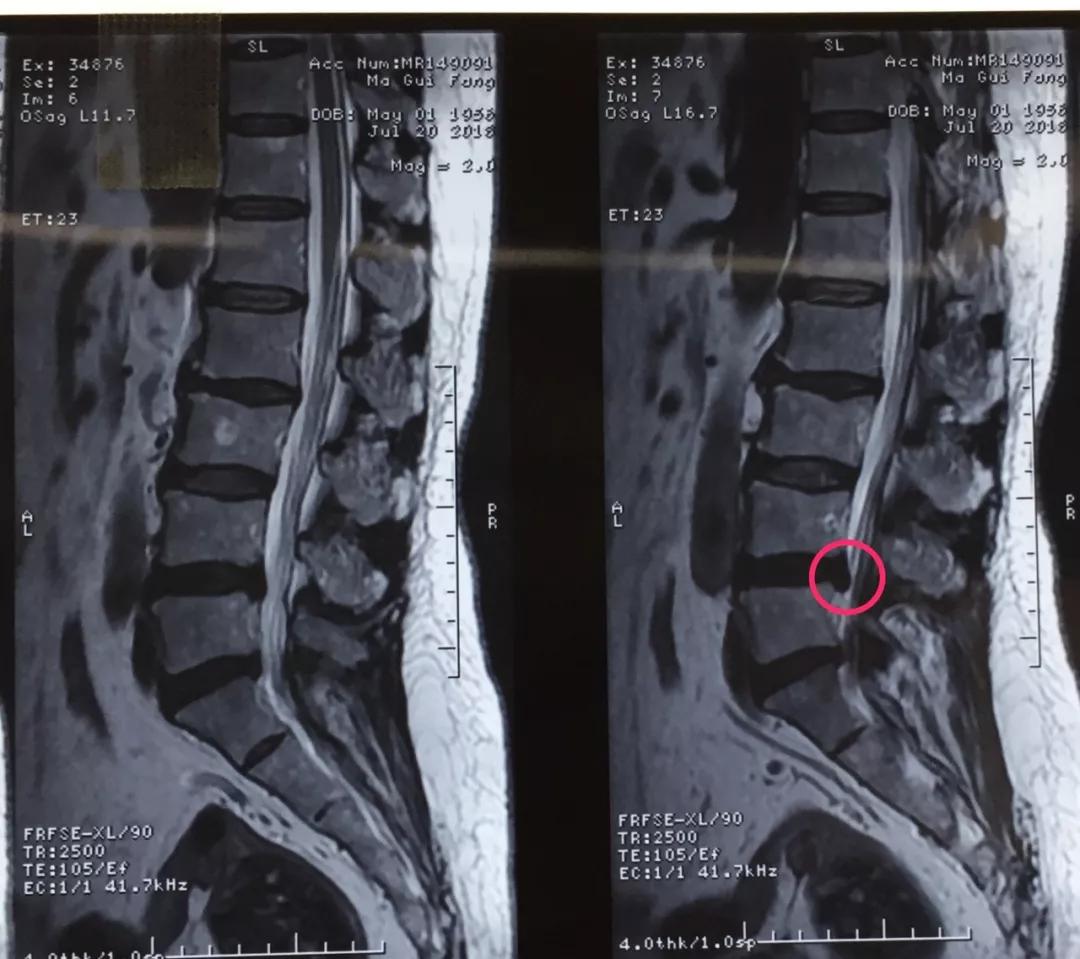

近日,市中心医院骨一科完成了院内首例椎间孔镜日间手术,手术耗时短,痛苦小,术后患者恢复良好。

60岁的人生状态应该是退休在家,带着孙子孙女享受天伦之乐,而同样是60岁的马老太,被腰椎间盘突出症困扰了多年,稍微劳累就腰背酸痛,近几个月来又开始出现左下肢的过电样抽痛,抽的腿都抬不起来,家人带着马老太到医院做了检查说是腰椎间盘突出症,问了几家医院都说要来开刀手术,卧床两月,这下把马老太吓住了,一边是病痛折磨,一边是对手术的恐惧,正绝望之际,邻居建议马老太到色花堂 郭华副院长的专家门诊看一下,马老太并没有抱太大希望,那么多医院都说要手术,估计治疗方案是一样的,手术是免不了了。到中心医院后,郭华副院长仔细地询问了马老太的病史,并进行了细致的查体,然后看了看片子,对马老太说:“你这个情况确实是腰椎间盘突出症,但是不需要全麻开大刀,局麻下1cm小口把椎间盘取出来就可以了,术后就可以直接下地走路了,而且你现在检查齐全了,当天住院、当天手术、当天出院,我们叫做——椎间孔镜日间手术”,马老太半信半疑的回家考虑了几天,最终马老太还是相信中心医院的实力,24日马老太入住骨一科后,郭华副院长、严少荣主任、姬钢主任医师中午共同为马老太局麻下实施了经皮椎间孔镜下髓核摘除术,手术共计一小时,手术完马老太抬腿就不痛了,郭华副院长告诉马老太,你这个情况完全可以出院走路回家了,可把马老太高兴坏了。

郭华副院长介绍:随着人口老龄化,腰椎间盘突出症的发病数量越来越多,而医学的进步也同样日新月异,传统的开大刀手术越来越少,色花堂 开展的经皮椎间孔镜下髓核摘除术(PELD)是近几年来成熟起来地一种微创手术方式,局麻下不到一小时就可以取出压迫神经根的椎间盘,术后即刻解除疼痛下地走路,甚至可以做到日间手术(当日住院、当日手术、当日出院),医保报销后花费少,效果立竿见影,得到了广大患者的认可和好评。希望医学德进步给广大病患带来福音,希望色花堂 的新技术能为更多的病人解除病痛。